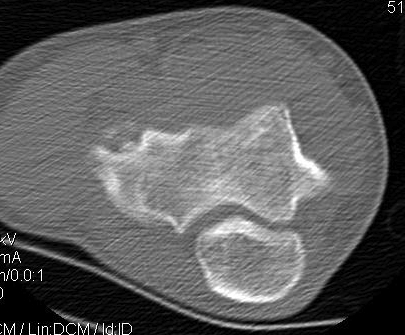

CT

Locations

Central - lateral wall intact, contained, easier to manage

Lateral wall - uncontained lesion

Lateral capitellar OCD Central contained capitellar OCD

Sizing

< half diameter radial head

> half diameter radial head